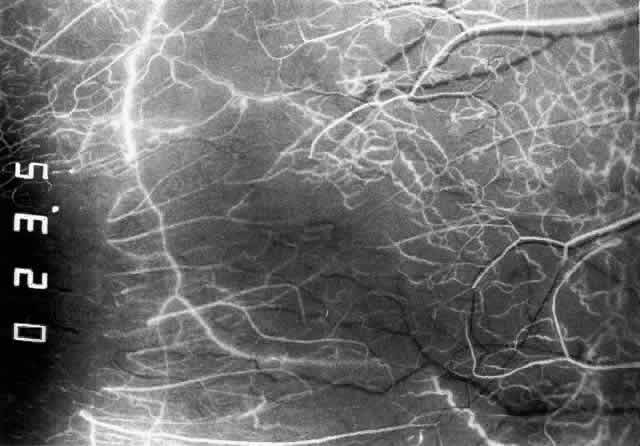

Simple and nodular episcleritis differ in their clinical courses, but in both the edema and infiltration are entirely within the episcleral tissues. The sclera is not involved. The maximum congestion is in the superficial episcleral network, with some slight congestion of the conjunctival vessels and deep episcleral vessels (Fig. 10). The intraocular structures are not involved in either variety, nor is the visual acuity affected. Anterior segment fluorescein angiography reveals a normal vascular pattern but a very rapid flow rate, with the whole transit of the dye being completed within 2 or 3 seconds (Figs. 11 and 12).

Fig. 11. Anterior segment fluorescein angiogram of a 45-year-old woman with simple episcleritis. At first transit of dye, all the vessels are dilated and filling simultaneously. However, the vascular pattern is not disturbed.

Fig. 12. Angiogram of the same 45-year-old woman in Figure 11 one second later. Within 1 second, all the vessels are filled and there is even, venular filling except in the deep episcleral plexus. This is the rapid filling pattern seen in all forms of episcleritis and in diffuse anterior scleritis.